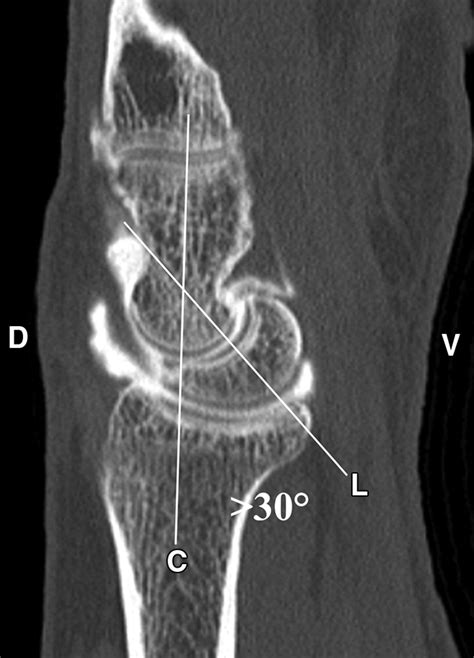

Diagnosing this condition requires a comprehensive physical examination combined with advanced imaging. Physicians typically rely on standard X-rays, which often reveal the characteristic gap in the scaphoid and the narrowing of the joint space. In more complex cases, a CT scan or MRI may be ordered to assess the exact degree of cartilage degradation and to plan potential surgical interventions.

• scaphoid nonunion advanced collapse radiology